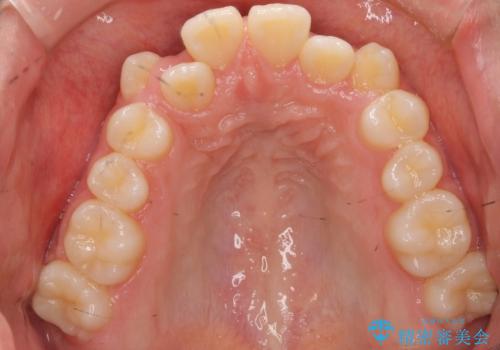

八重歯や、前歯のオープンバイト(開咬)の症状があり、マウスピース(インビザライン)矯正単独では治すのが難しい症状が複合していました。

八重歯や抜歯したスペースの閉鎖をワイヤー矯正で前半行い、治療後半は目立たないインビザラインでかみ合わせを調整しました。

上の奥歯を後ろ下げるために、矯正用ミニスクリューを使用しています。